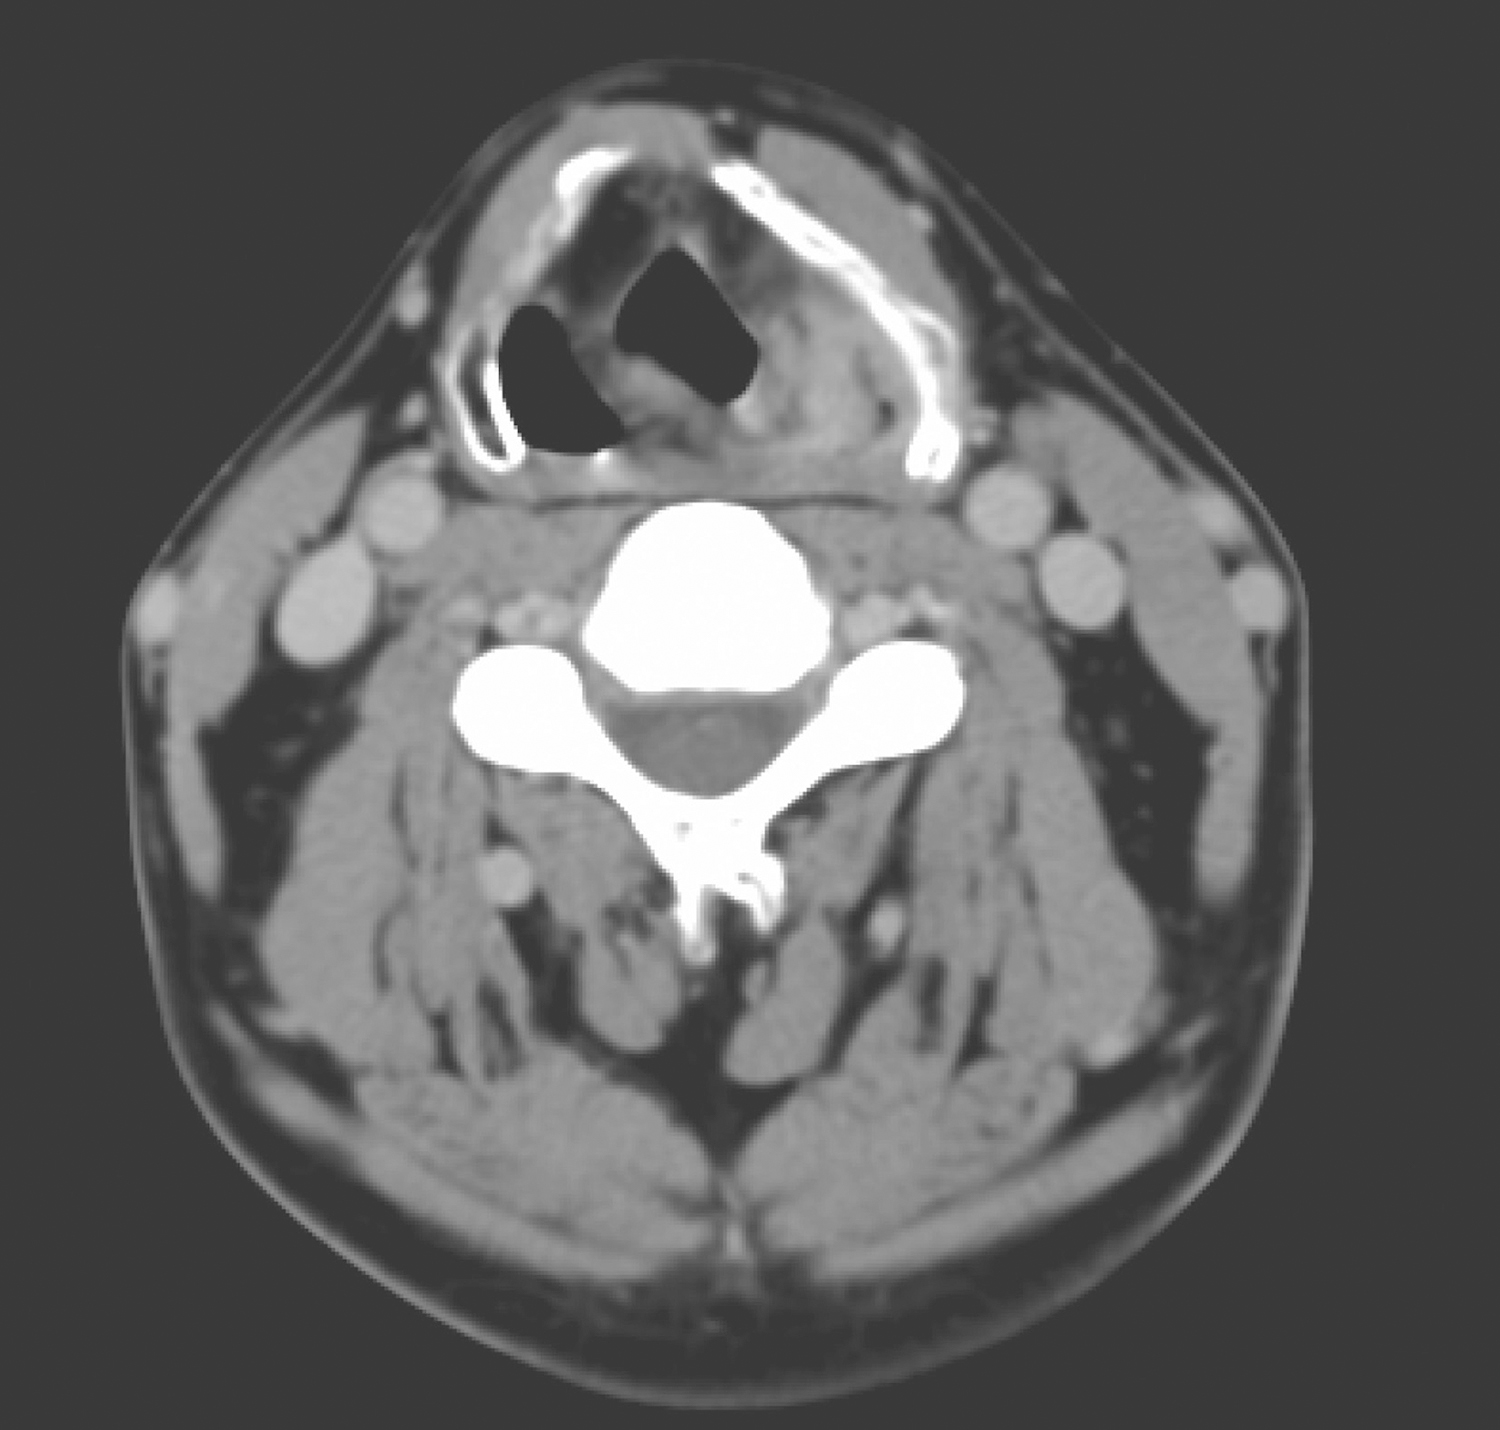

2.2014年12月1日颈胸部强化CT:左侧梨状窝内侧壁、左侧杓会厌皱襞局部软组织增厚,约2cm×2cm,形态不规则,可见强化(图2)。左侧Ⅲ区颈鞘前方可见肿大淋巴结一枚,约2cm大小,轻度强化(图3),余颈部、纵隔未见肿大淋巴结,肺部未见占位病变。

图2下咽左侧梨状窝肿物

影像学诊断:

(1)下咽左侧梨状窝肿物,结合临床恶性肿瘤不除外。